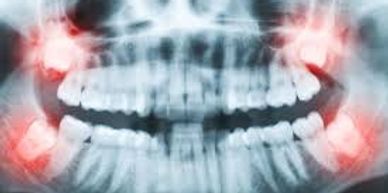

Wisdom Tooth Extraction